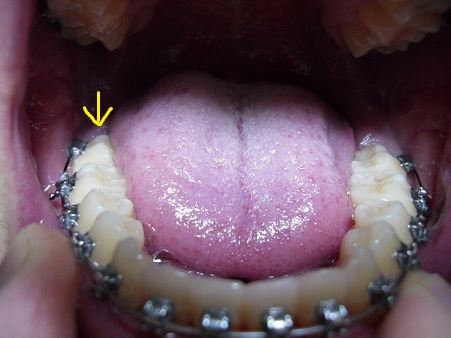

안쪽어금니 누워있는게말이죠.

입을다물면 다른치아보다 먼저닿아서 입이 다 안다물립니다.

다른치아보다 먼저 닿아서 지금 입안은 벙 떠있는상태구요.

심지어 저 어금니외엔 다른치아는 단 1개도 서로닿질않아서 음식물씹을때 하나도 끊어지는게없습니다.

정말 입 제대로다물려고하면 먼저 어금니가 닿아버리는데 안건들어도 되는건가요

이건 지난번 사진이긴한데 계속 이렇게 고무줄만 걸고있습니다.